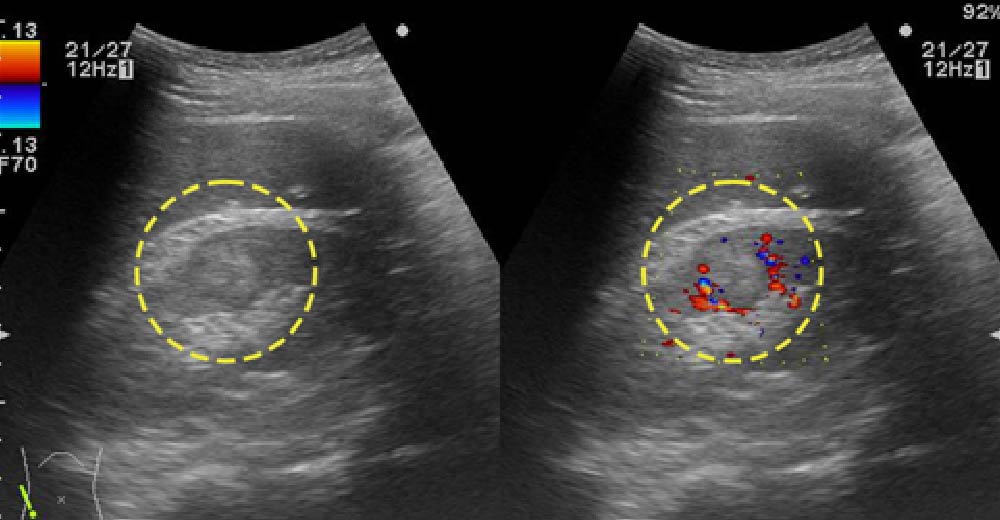

膀胱がん症例です。

エコーで膀胱内に血流信号のある腫瘤と、CTで造影効果のある膀胱内腫瘤が確認されます。

膀胱がん 膀胱がん 膀胱がん 膀胱がん